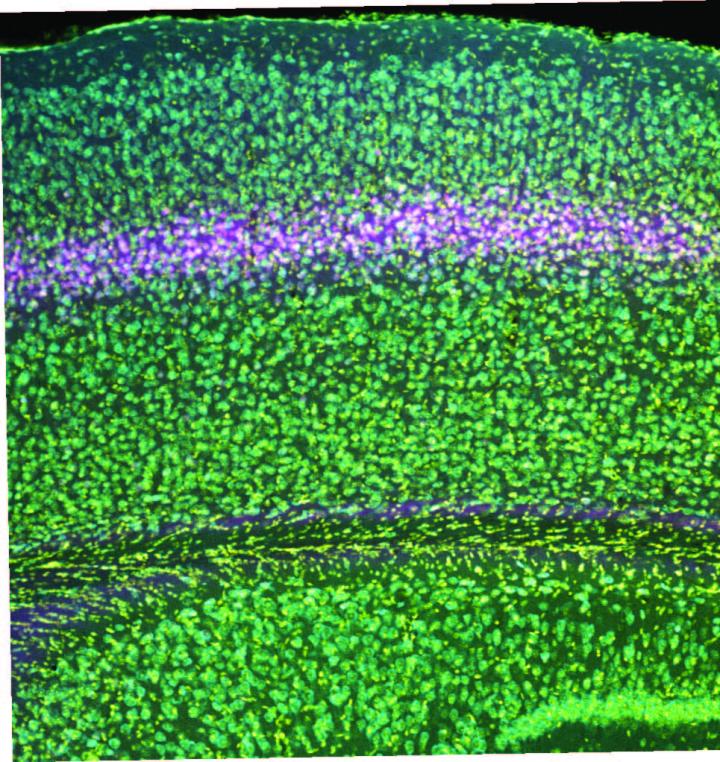

image: Researchers used a genetic technique to knock out NMDA receptors in layer 4 of the visual cortex of mice.

Bear Lab/ Picower Institute for Learning and Memory

To perform the study, Bear Lab postdoc and lead author Ming-fai Fong and used a genetic technique to specifically knock out NMDA receptors in excitatory neurons in layer 4 of the visual cortex of mice. Armed with that tool, she could then investigate the consequences for visual recognition memory and "monocular deprivation," a lab model for amblyopia in which one eye is temporarily closed early in life. The hypothesis was that knocking out the NMDA receptor in these cells in layer 4 would prevent SRP from taking hold amid repeated presentations of the same stimulus, and would prevent the degradation of vision in a deprived eye as well as the commensurate strengthening of the unaffected eye.